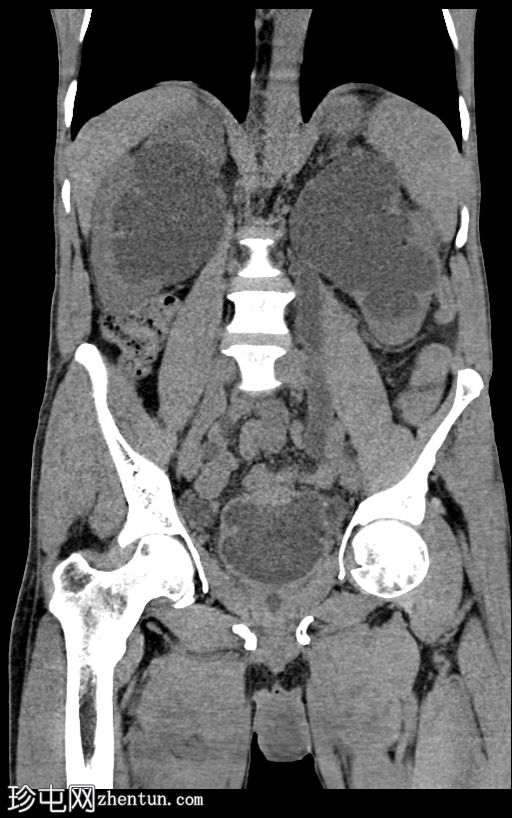

冠状位

平扫

膀胱内可见一枚较大的高密度结石(轴位、冠状位、矢状位),大小约8 × 5.6 × 5.1 cm,伴膀胱壁弥漫性增厚和小憩室。

双侧中重度输尿管肾积水,肾实质厚度减薄,左侧更为明显。双侧输尿管迂曲(右侧、左侧),前列腺尿道轻度扩张。双侧未见肾内或输尿管结石。

本病例展示了一例巨大的膀胱结石导致慢性膀胱出口梗阻,并继发双侧输尿管肾积水。